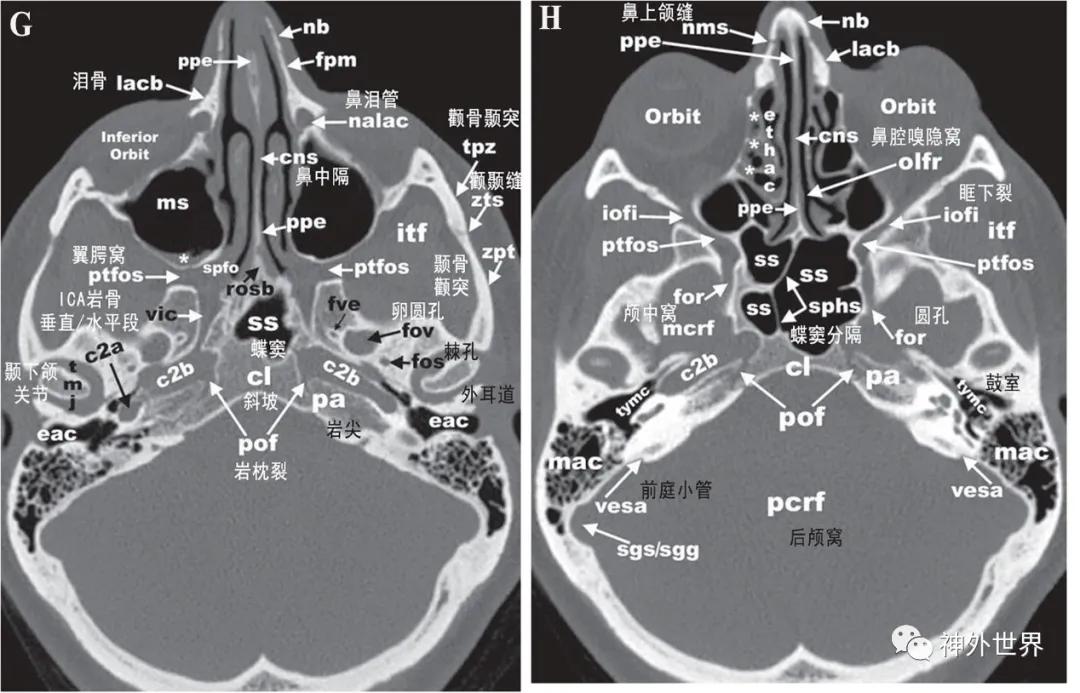

图3:颅底CT骨性横断面影像解剖